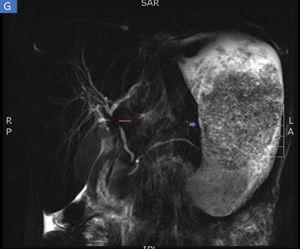

The biopsies taken at upper endoscopy showed severe chronic inflammatory changes, lymphoplasmacytic infiltrate, with deep, extensive ulcerated areas in the esophagus, stomach, and duodenum, and no evidence of dysplasia or malignancy. The immunohistochemical study ruled out a neoplastic process of adenocarcinoma or lymphoma and the Ziehl-Neelsen and methenamine silver stains were negative for tuberculosis and a fungal infection, respectively (Fig. 2). Due to the high suspicion of Crohn’s disease, we ordered a magnetic resonance enterography (MRE) study to evaluate disease extension, ruling out involvement of the rest of the small bowel and lower digestive tract. The extent and depth of the gastric lesions were striking in the MRE study, as was the presence of an inflammatory stricture at the confluence of the hepatic ducts and the proximal common bile duct (Fig. 3).

Magnetic resonance enterography identifying severe inflammatory changes and thickening of the stomach (short arrow), as well as the incidental identification of a severe stricture, with an inflammatory aspect, at the confluence of the hepatic ducts and the proximal common bile duct, consistent with primary sclerosing cholangitis (long arrow).